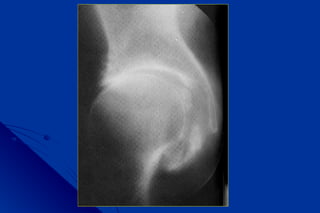

Signes radiologiques communsSignes radiologiques communs

à toutes les coxarthrosesà toutes les coxarthroses

 pincementpincement localisélocalisé dede

l’interlignel’interligne en général supéro-en général supéro-

externeexterne

 OstéophytoseOstéophytose à la périphérie desà la périphérie des

surfaces cartilagineusessurfaces cartilagineuses

 Condensation osseuse sousCondensation osseuse sous

chondralechondrale

 GéodesGéodes